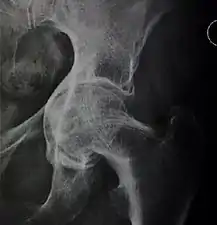

Crowe classification

In 1979 Dr. John F. Crowe et al. proposed a classification to define the degree of malformation and dislocation. Grouped from least severe Crowe I dysplasia to most severe Crowe IV.[13] This classification is very useful for studying treatment results.

Rather than using the Wiberg angle because it makes it difficult to quantify the degree of dislocation they used 3 key elements to determine the degree of subluxation: A reference line at the lower rim of the "teardrop", junction between the femoral head and neck of the respective joint and the height of the pelvis (vertical measurement). They studied anteroposterior pelvic x-rays and drew horizontal lines through the lower rim of a feature called "teardrop". The distance between this line and the middle lines of the junction between femur head and neck gave them a measure of the degree of femur head subluxation. They further established that a "normal" diameter of the femur head measures 20% of the height of the pelvis. If the middle line of the neck-head junction was more than 10% of the pelvis height above the reference line they considered the joint to be more than 50% dislocated.[13]

The following types resulted:[13]